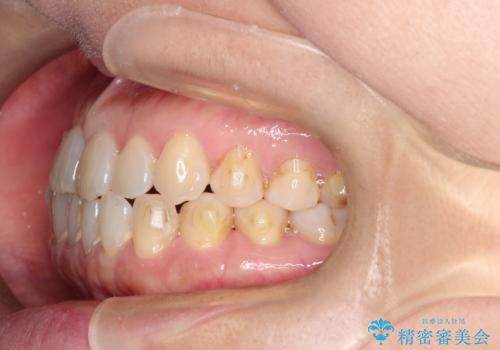

前歯の隙間 インビザラインによる目立たない成人矯正

- 前歯の隙間を気にされて来院されました。

インビザラインにて、目立たずに矯正治療を行うこととしました。

歯と歯の間にある隙間を閉じるのは、インビザラインでもしっかり治療できます。